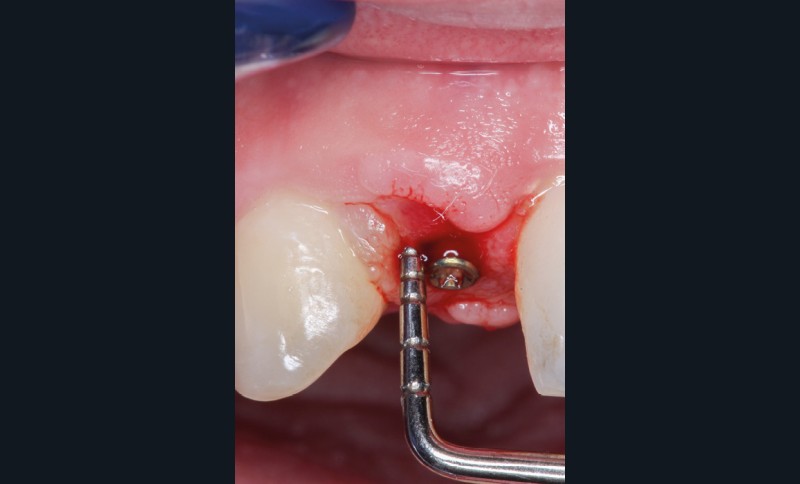

Le projet prothétique pré-implantaire [11] est également l’une des clés du succès ; il doit permettre un positionnement tridimensionnel optimal de l’implant, notamment avec un environnement tissulaire adéquat ; selon la littérature, 2 mm de tissu kératinisé sont nécessaires autour des implants pour fonctionner comme un bouclier autour de lui [12] (fig. 3).